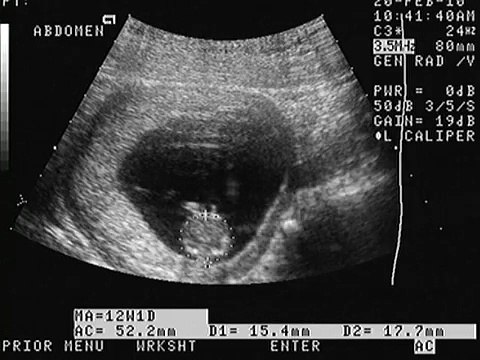

¿Por qué la paciente se debe realizar un ultrasonido entre las semanas 30-32 de embarazo?